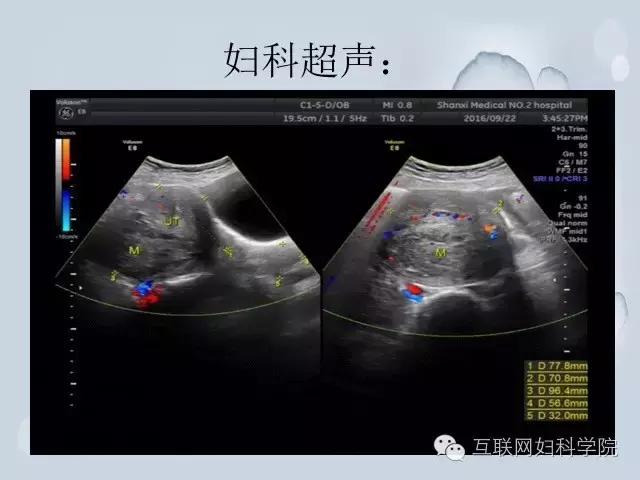

本台手术病例: